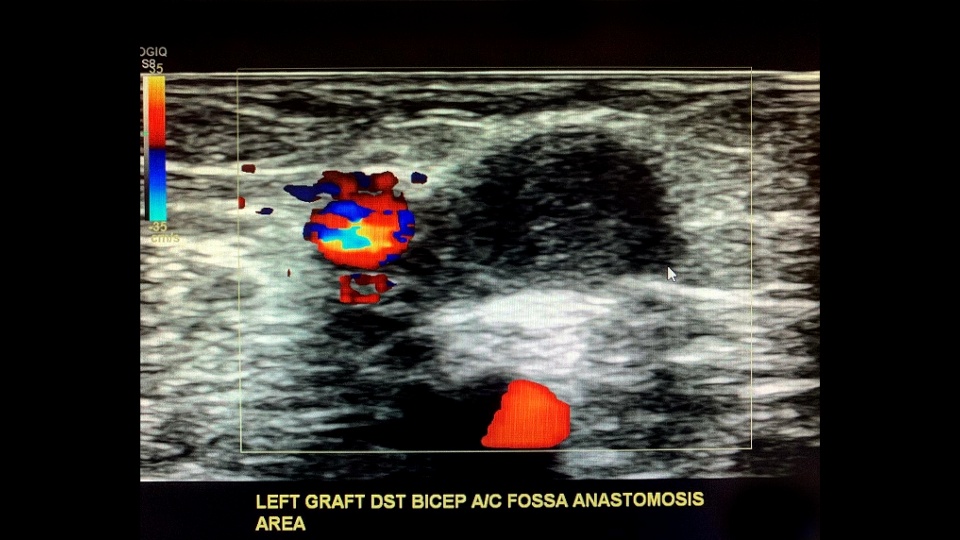

This patient has a left arm radial-cephalic vein AV anastomosis (aka Brescia-Cimino) which is the most common AVF connection.

Evaluate the patency and maturity of the fistula while also monitoring the inflow/outflow streams as well as assessing the site of anastomosis.

In this case the radial artery is the inflow; and the forearm cephalic vein the outflow.

Next we assess the outflow stream (venous side) starting with the subclavian/cephalic vein confluence at the shoulder level followed by the bicep and forearm segments of the outflow stream evaluating for abnormalities such as thrombus, stenosis, occlusions, PSA/aneurysms, etc.

Sample the venous anastomosis side a few times the highest sampled here is PSV/EDV as 500/170 cm/s.

Make sure to measure the size of the anastomosis before completing the exam.